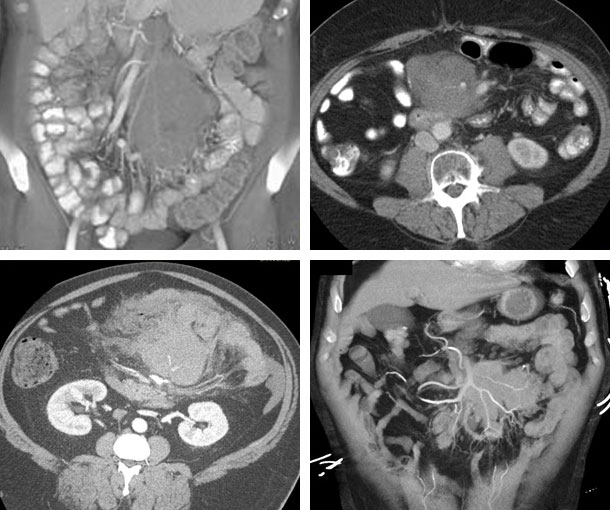

Mesenteric Lymphoma CT Findings

- Single or multiple homogeneous masses

- Can be either round/oval or irregularly shaped

- Mild enhancement

- Increased attenuation of mesenteric fat

- Areas of low attenuation due to necrosis

- Masses surround mesenteric arteries and veins (two masses surrounding the mesenteric vessels may be interpreted as the “sandwich sign”)

- Mesenteric lymphoma can be small or grow to be quite large

- Displacement or infiltration of the bowel is common